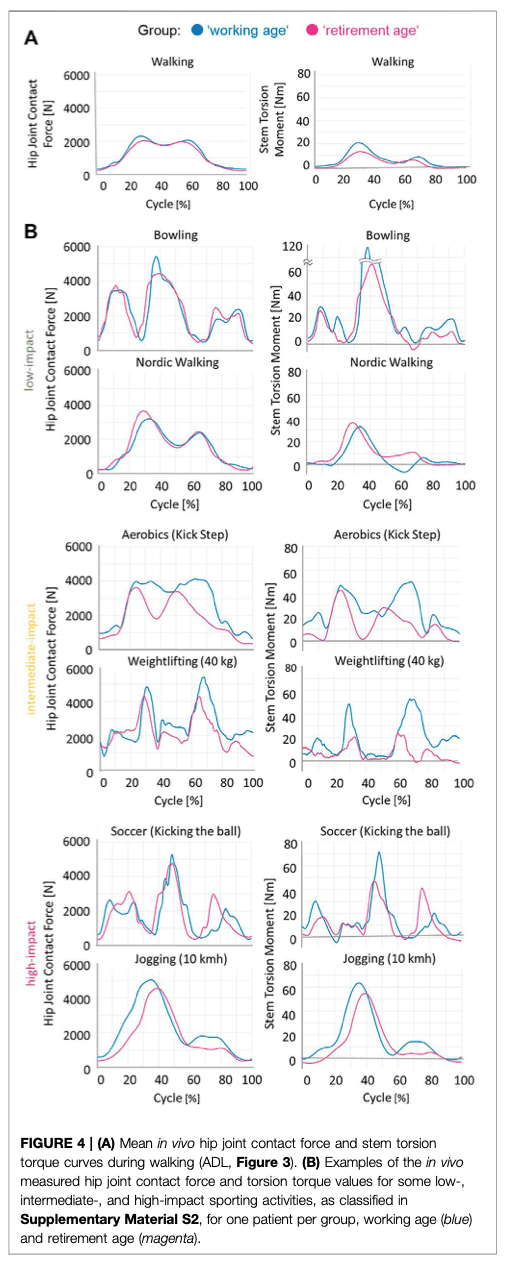

这个汇总表有话要说。 2022 年,本德测量了活体关节接触力和扭转力矩,发现保龄球等被认为是低冲击力的活动,与高冲击力的足球相比,会产生更高的关节接触力和扭转力矩。 此外,他们还发现体重和体重指数也会影响日常活动中的这些力。